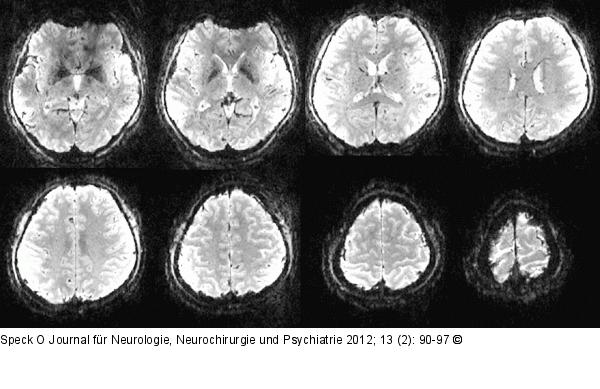

Abbildung 8: Single-shot-Echo-Planar Axiale „Single-shot“-Echo-Planar-Daten mit 1 mm isotroper Auflösung. Die Messzeit beträgt lediglich 50 ms pro Schicht (8 Schichten aus einem Datensatz von 60 Schichten). Die Voxelgröße ist gegenüber üblichen fMRT-Auflösungen von 2,5–3 mm um etwa das 20-Fache reduziert. Eine Zuordnung neuronaler Aktivierung zu anatomischen Strukturen kann somit ohne die Notwendigkeit einer weiteren Aufnahme erreicht werden. |

Axiale „Single-shot“-Echo-Planar-Daten mit 1 mm isotroper Auflösung. Die Messzeit beträgt lediglich 50 ms pro Schicht (8 Schichten aus einem Datensatz von 60 Schichten). Die Voxelgröße ist gegenüber üblichen fMRT-Auflösungen von 2,5–3 mm um etwa das 20-Fache reduziert. Eine Zuordnung neuronaler Aktivierung zu anatomischen Strukturen kann somit ohne die Notwendigkeit einer weiteren Aufnahme erreicht werden. |